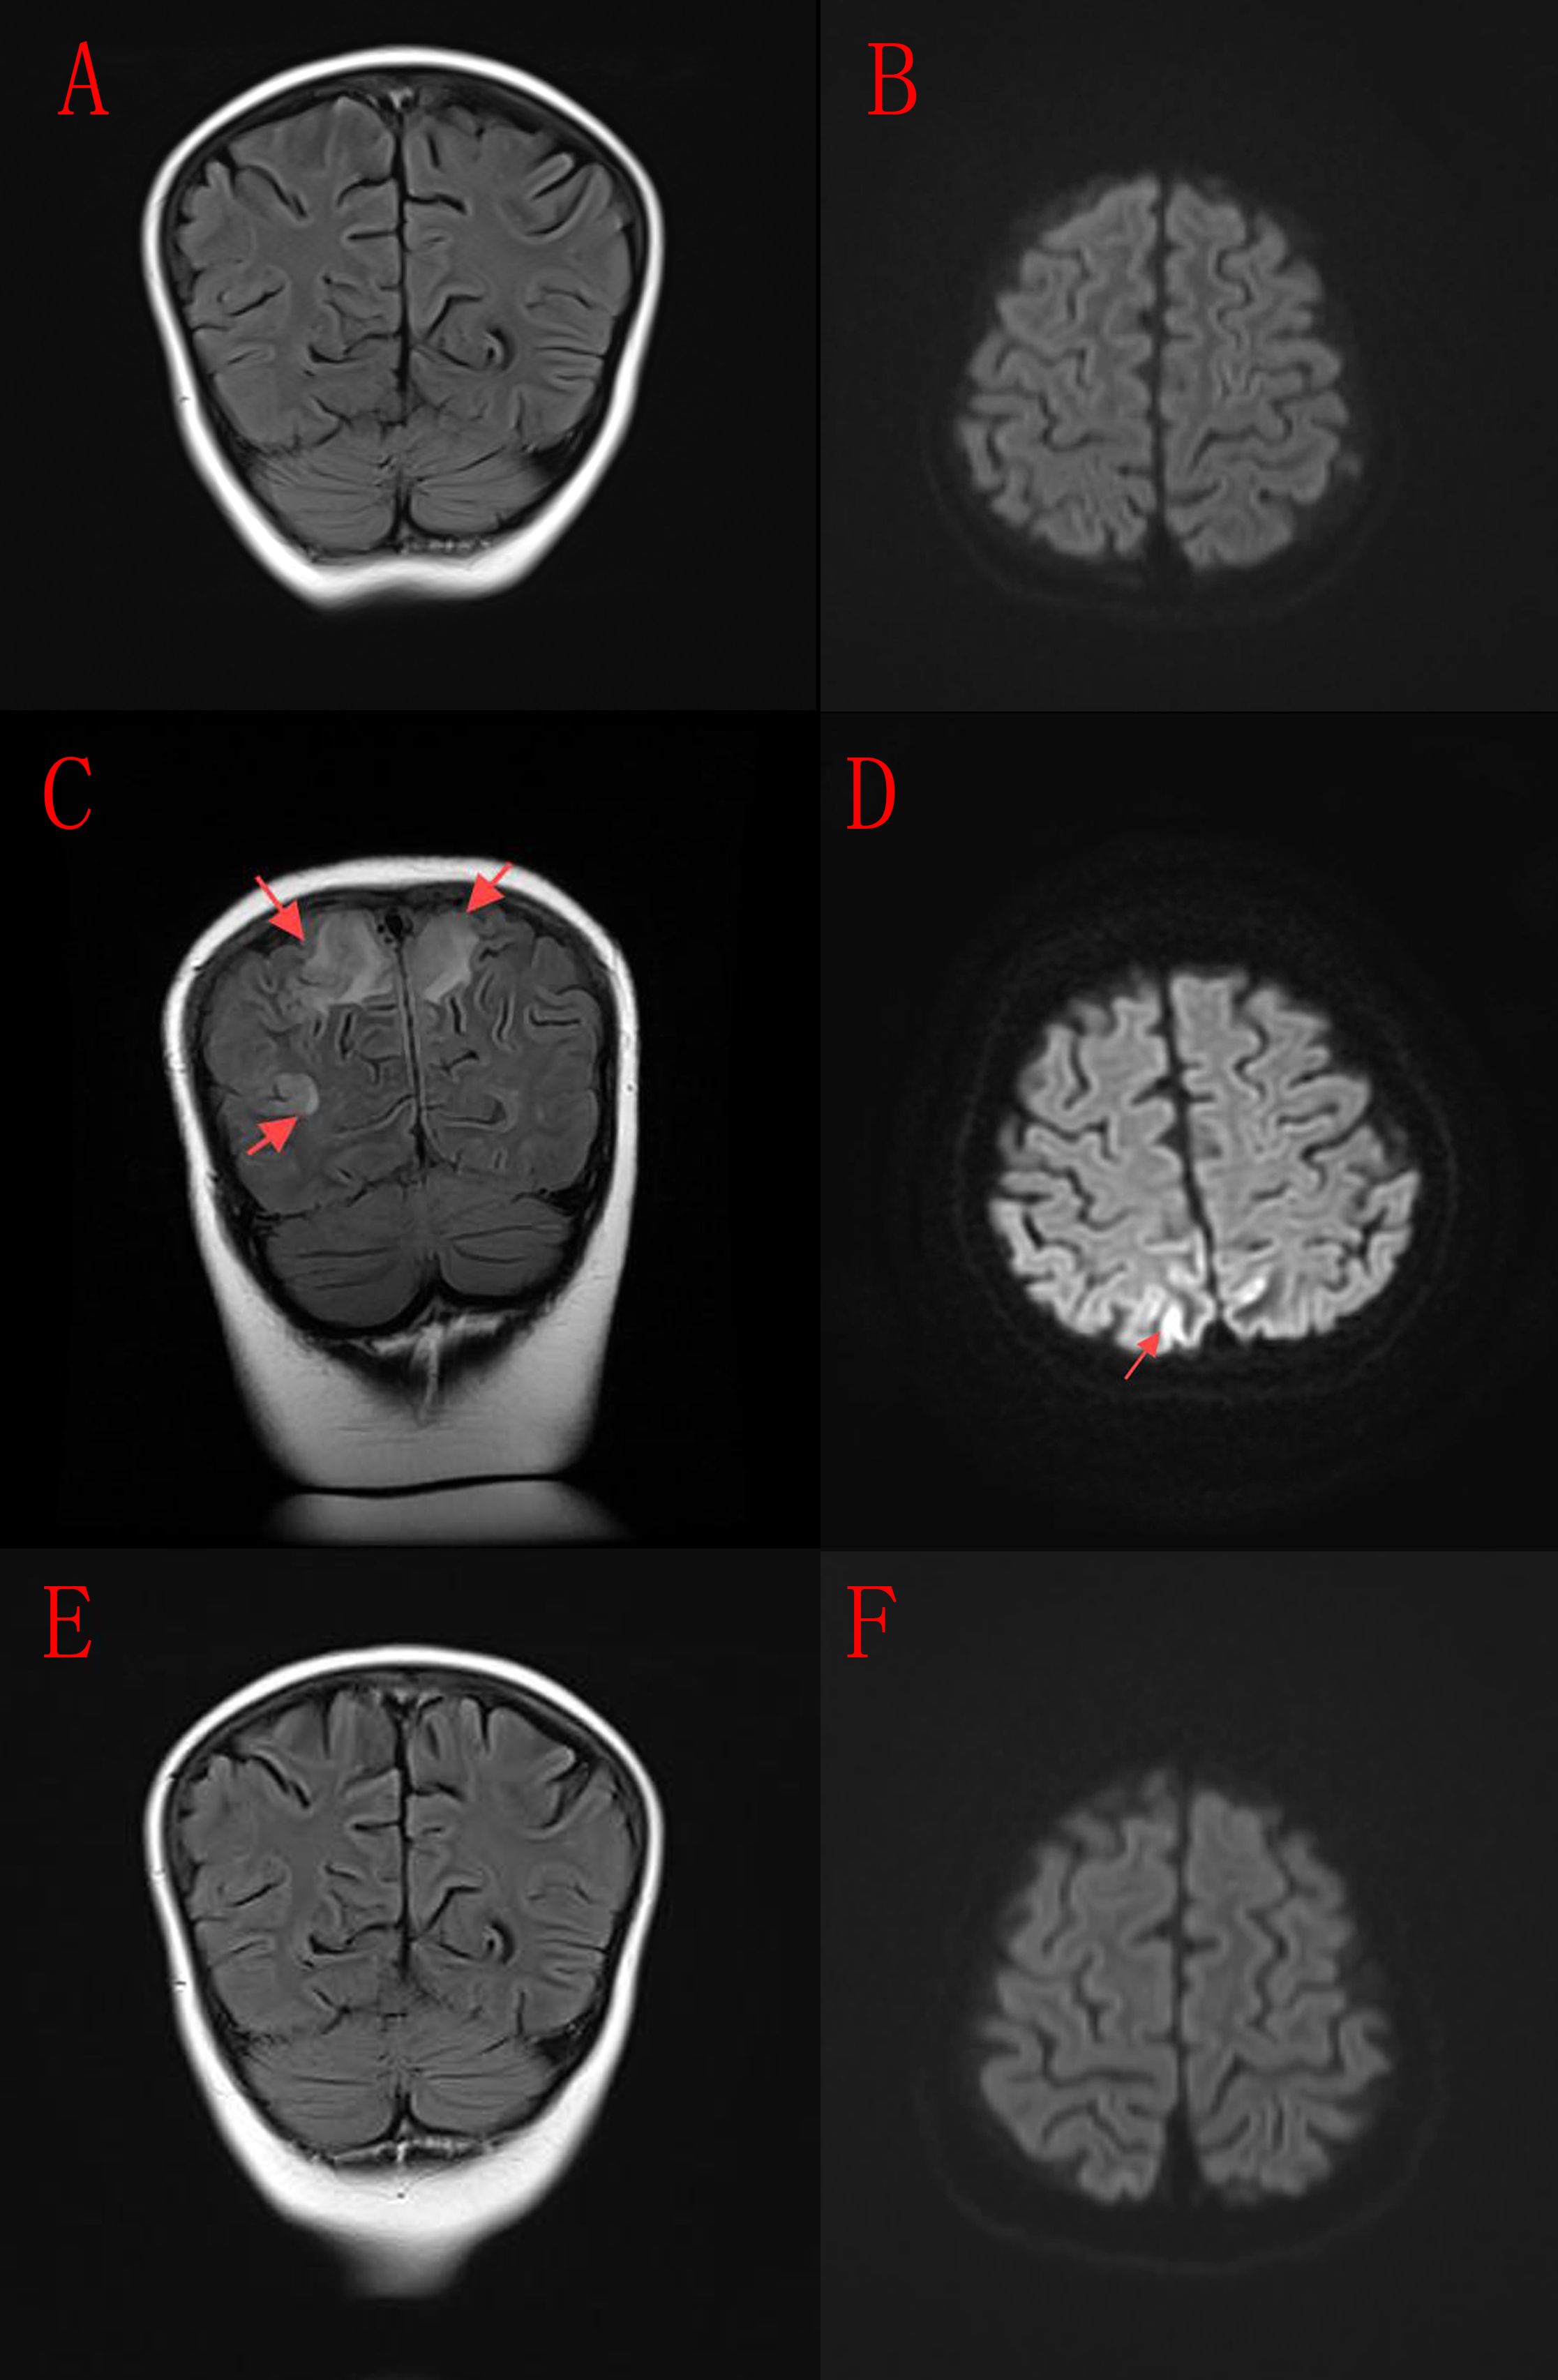

Abstract: Objective: As a critical immune checkpoint, cytotoxic T-lymphocyte-associated protein 4(CTLA-4)deficiency is a well-established cause of inborn errors of immunity. This study characterizes a novel CTLA-4 deletion variant identified in a pediatric case of refractory autoimmune hemolytic anemia (AIHA), with the aim of delineating the clinical profile and elucidating the underlying pathogenic mechanism. Methods: Trio-based whole-exome sequencing (WES) was performed on peripheral blood samples from a 6-year-old female with refractory AIHA and her parents. Candidate variants were validated by Sanger sequencing. Structural modeling of mutant CTLA-4 was conducted, followed by in vitro functional assays in 293T cells to assess mRNA transcription (qPCR) and protein expression (Western blot). Results: A CTLA-4 (c.362_391del) variant was identified within the immunoglobulin V-set domain of the CTLA-4 protein. In vitro experiments demonstrated significant reductions in both mRNA and protein expression levels caused by this variant. Conclusion: The CTLA-4 (c.362_391del) variant may contribute to refractory AIHA in children. This case highlights the potential necessity of including CTLA-4 variants in the differential diagnosis of pediatric AIHA, particularly when conventional therapies prove ineffective, and warrants further validation in larger cohorts.